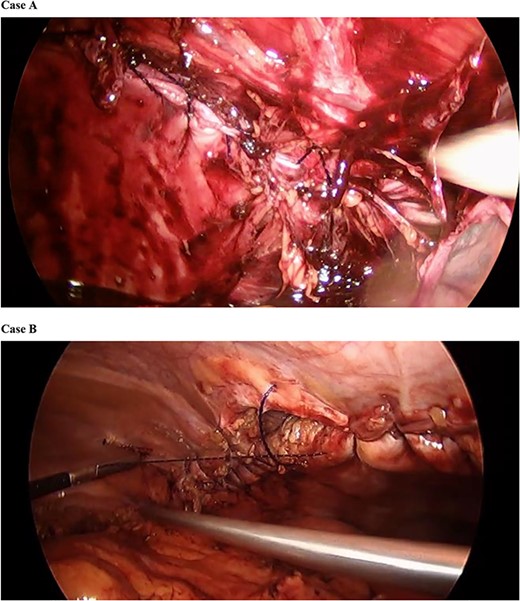

Next, attention was directed to mesh reinforcement of the incisional hernia. We placed a 15 × 10 cm monofilament macroporous composite mesh (Symbotex™; Covidien Medtronic, Mansfield, MA) to reinforce the suture repair of her left flank incisional hernia. A centering stitch was placed allowing the mesh to be pulled up to the center of the defect repair, and thereafter, the mesh was secured to the abdominal wall with absorbable tacks (AbsorbaTack™; Covidien Medtronic, Mansfield, MA) (Fig. 3).

Monofilament macroporous composite mesh was placed over the abdominal wall defect with 5 cm overlap to reinforce the repair. Mesh was secured with a laparoscopic absorbable tack fixation.

We similarly used #1 Stratafix suture, except in this case we ran sutures from both ends of the defect until they met at the middle of the hernia. We also placed transfascial sutures across the long axis of the repair to offload tension from the tissue approximation.